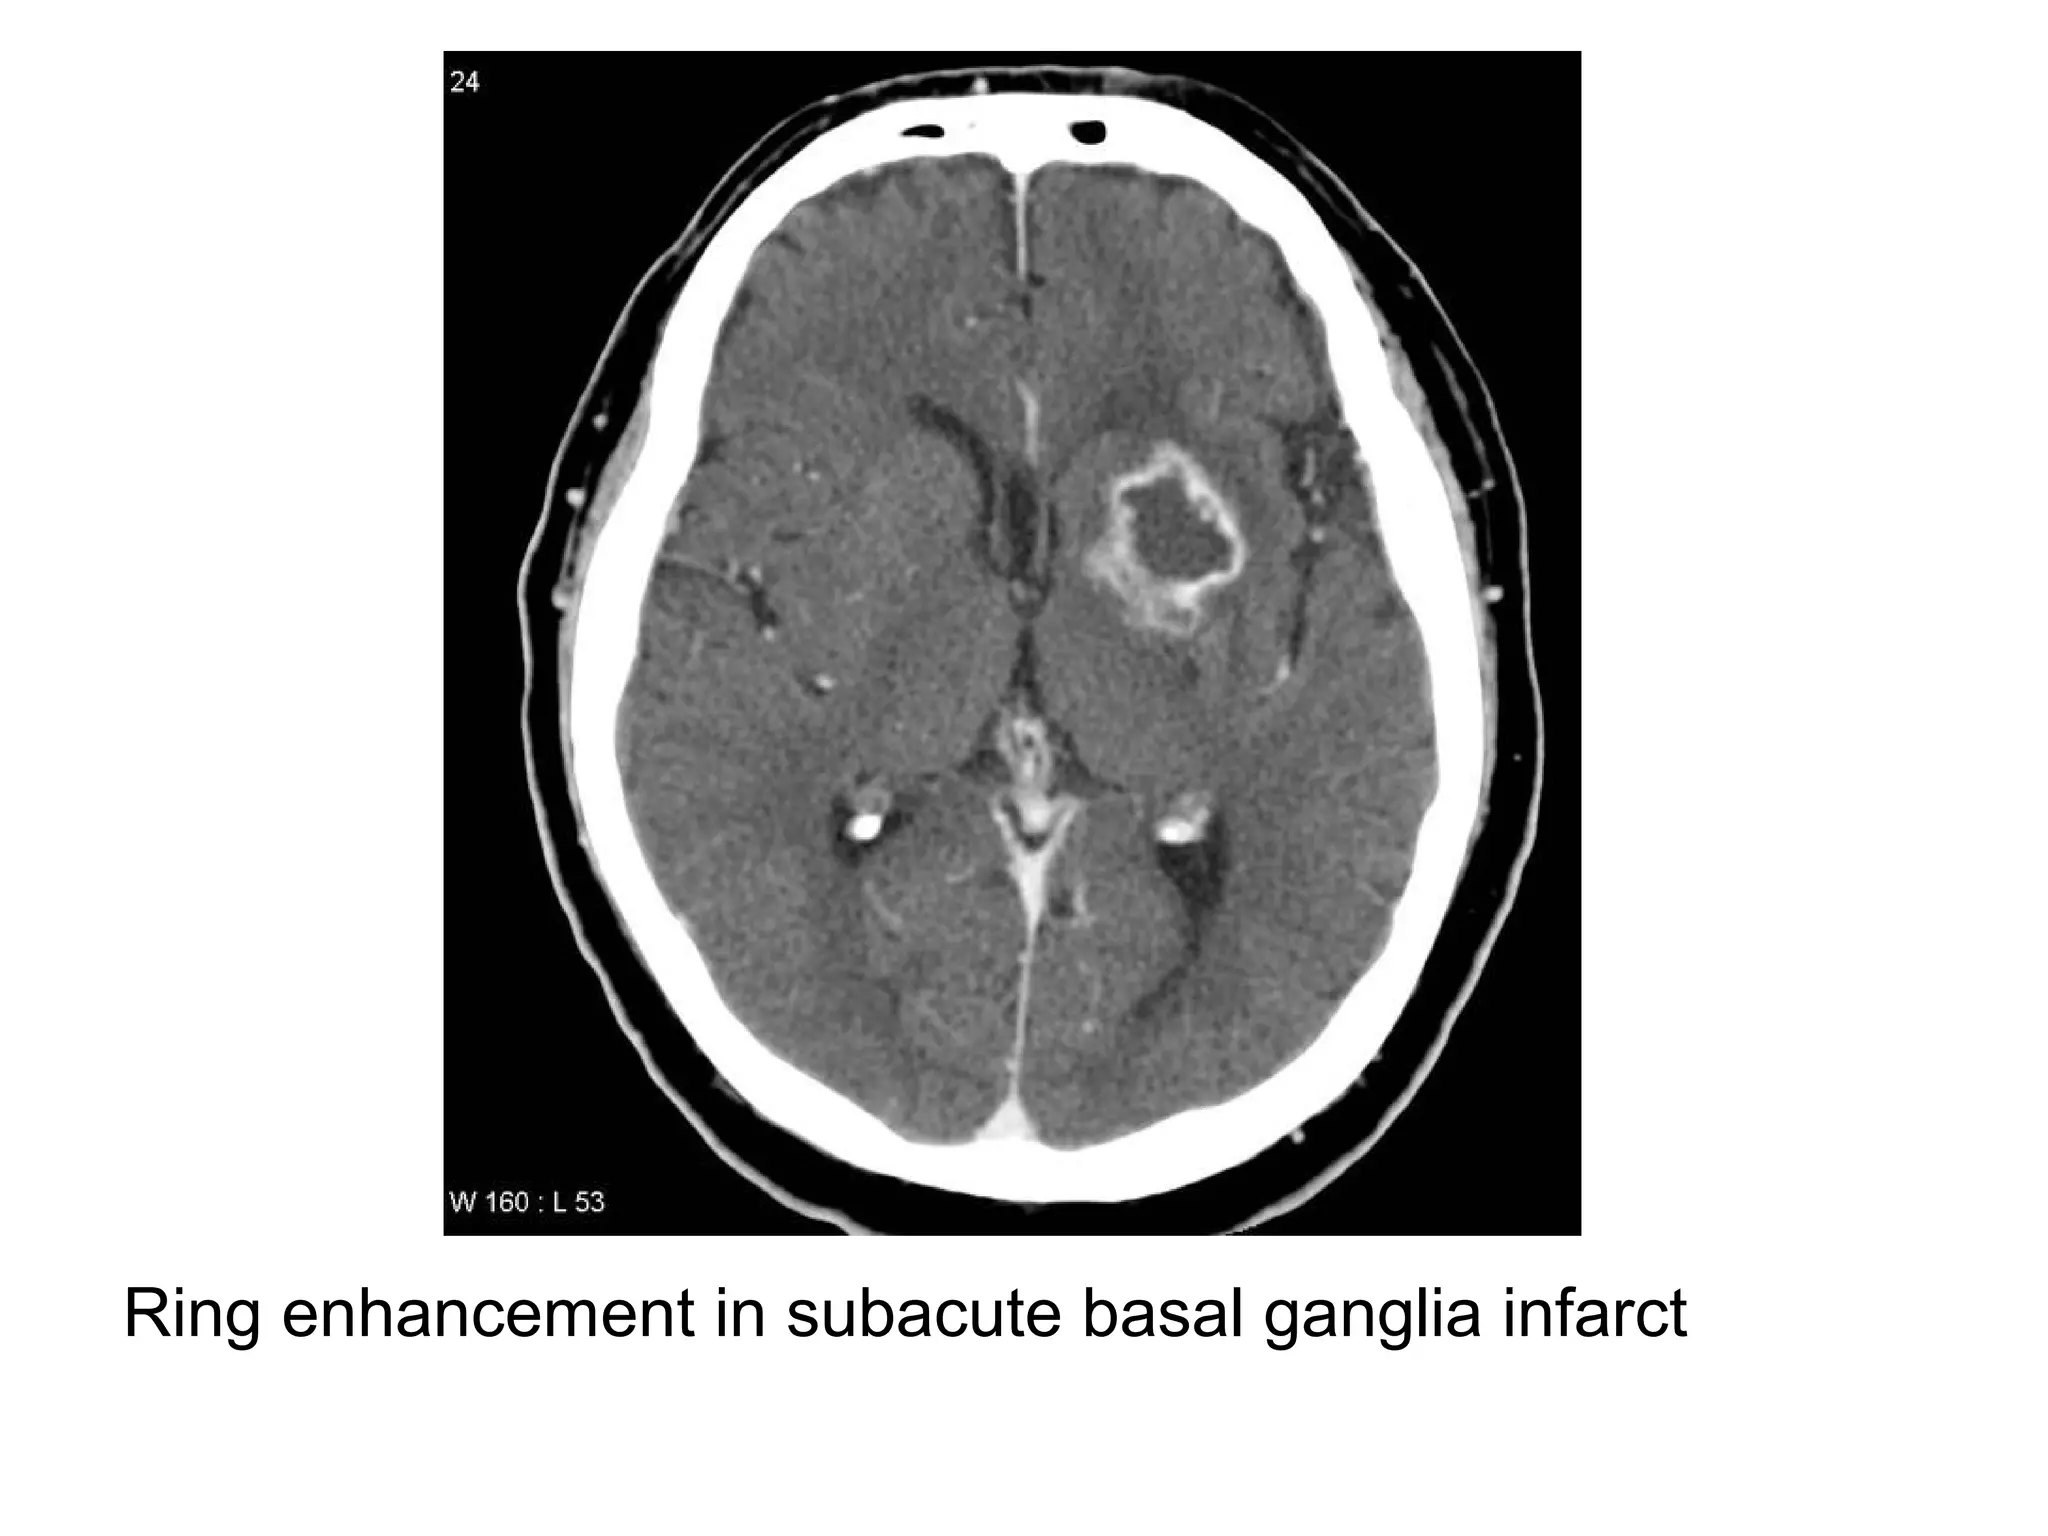

4-Infarct (although subacute cortical infarcts often show

gyral enhancement, ring enhancement can be seen in

subacute basal ganglia infarcts, in contrast to neoplasm

& infection, a subacute infarct doesn’t have significant

mass effect)

Ring enhancement in subacute basal ganglia infarct